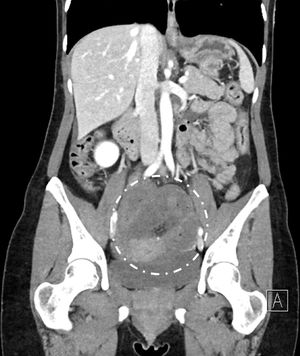

En urgencias, la paciente presenta distensión abdominal con dolor en el hemiabdomen inferior e irritación peritoneal a la palpación. La analítica muestra un síndrome inflamatorio con leucocitosis moderada (12.460G/l de glóbulos blancos), una proteínaC reactiva normal, LDH a 232U/l y anemia leve a 10,9g/dl de hemoglobina. La tomografía computarizada abdominal muestra una obstrucción intestinal mecánica con dilatación y signos de necrosis intestinal (fig. 1) con una sospecha de hernia interna estrangulada con zona de transición localizada en la pelvis. Se decide ingresar a la paciente y realizar intervención, y aplicamos el protocolo COVID-19 de nuestra institución, que conlleva realizar un test nasofaríngeo y una TC torácica; las pruebas complementarias no muestran signos de COVID-19 (resultados negativos).

El abordaje fue laparoscópico, encontrando un segmento intestinal de íleon necrótico de 70cm debido a una herniación interna de este en un foramen del LAUO izquierdo (fig. 2a). Por laparoscopia localizamos el defecto en el LAUO izquierdo de tipo ventana, según la clasificación de Hunt (fig. 2b)2. En vista de la dilatación del yeyuno proximal a la hernia y la necrosis ileal observada, se decidió reconversión en laparotomía pero con una incisión adaptada de 10cm. Se resecó el intestino necrótico realizando una anastomosis mecánica latero-lateral a unos 30cm de la válvula de Bauhin. El defecto del LAUO de 3cm (tipo3 según la clasificación de Cilley, fig. 2b)3 se cerró con una sutura de hilo barbado 3-0 no absorbible.